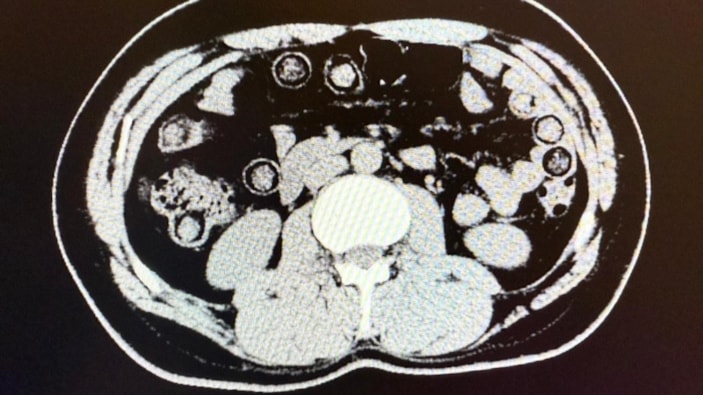

Hastanede yapılan iç beden muayeneleri sırasında çekilen tomografi görüntülerine göre uyuşturucu madde yuttukları tespit edilmiştir. Hastanede yapılan tespit sonrasında şahısların midelerinde toplam 94 adet kapsül içerisinde daralı ağırlıkları 928 gram gelen metamfetamin maddesi ele geçirilmiştir. Şüpheli şahıslar hakkında ‘uyuşturucu ve uyarıcı madde ticareti’ suçundan işlem yapılmak üzere Cumhuriyet Başsavcılığına intikal ettirilmiş ve çıkarıldıkları mahkemece tutuklanmışlardır.